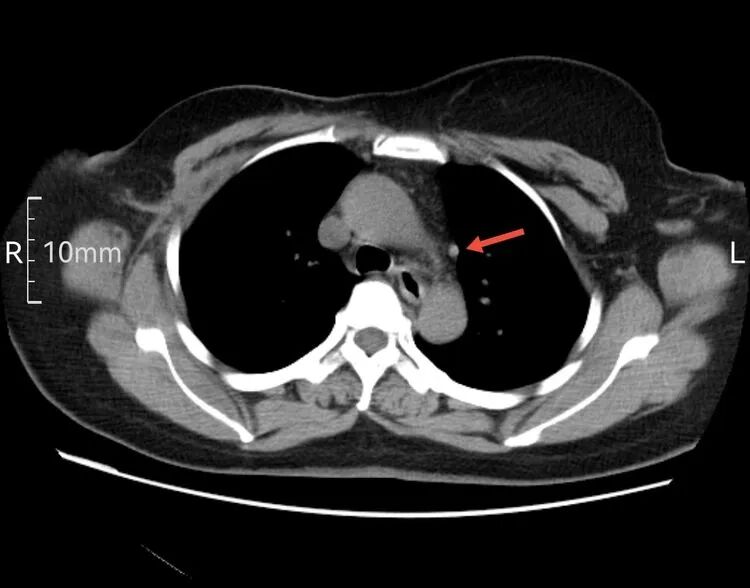

以下是患者的CT表现:

为什么建立双输液通道输液港 偶遇“双上腔静脉”_https://www.jmylbn.com_新闻资讯_第3张

箭头所指为左侧“上腔静脉”走行  虽然过程不寻常,但在血管造影辅助下显示其“真容”后,导管经左侧颈内静脉,避开变异的“左上腔静脉”并通过左侧头臂干,导管头端留置在正常的上腔静脉内。成功给予患者植入左侧胸壁港。